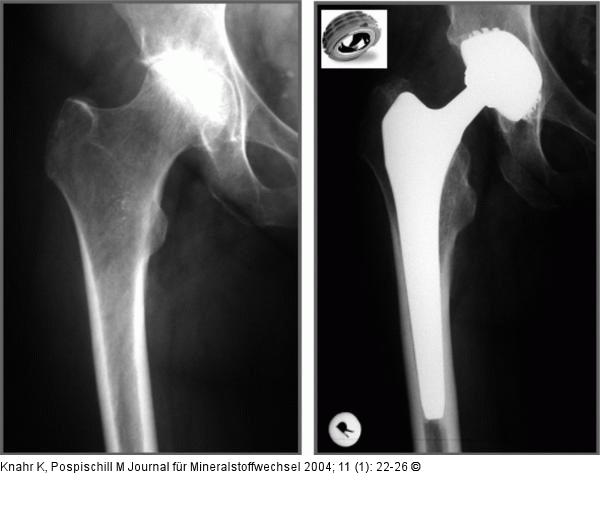

Abbildung 3: Hüftgelenk Metall-Metall-Gleitpaarung bei 48jährigem Mann mit hochgradiger Coxarthrose |

Abbildung 3: Hüftgelenk

Metall-Metall-Gleitpaarung bei 48jährigem Mann mit hochgradiger Coxarthrose |